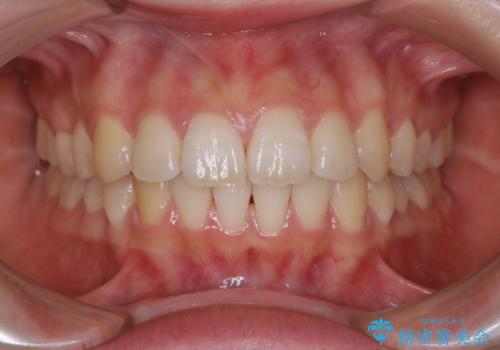

インビザラインで目立たない矯正 ガタガタの歯並びをきれいな歯並びへ